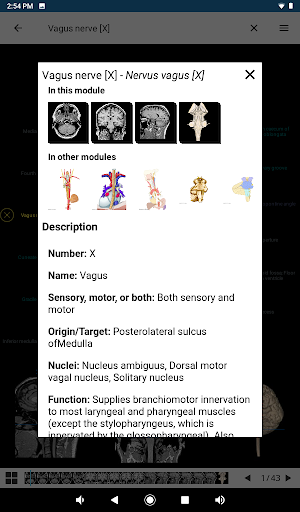

e-Anatomy memiliki lebih dari 26.000 gambar yang berisi serangkaian gambar dalam tampilan aksial, koronal, dan sagital serta radiografi, angiografi, gambar diseksi, bagan anatomi, dan ilustrasi. Semua gambar medis diberi label dengan cermat, lebih dari 967.000 label tersedia dalam 12 bahasa termasuk Terminologia Anatomica Latin.

- Ketuk label untuk menampilkan struktur anatomi

*Peningkatan tampilan detail bagian anatomi untuk memudahkan identifikasi dalam gambar modul saat ini dan modul lainnya.